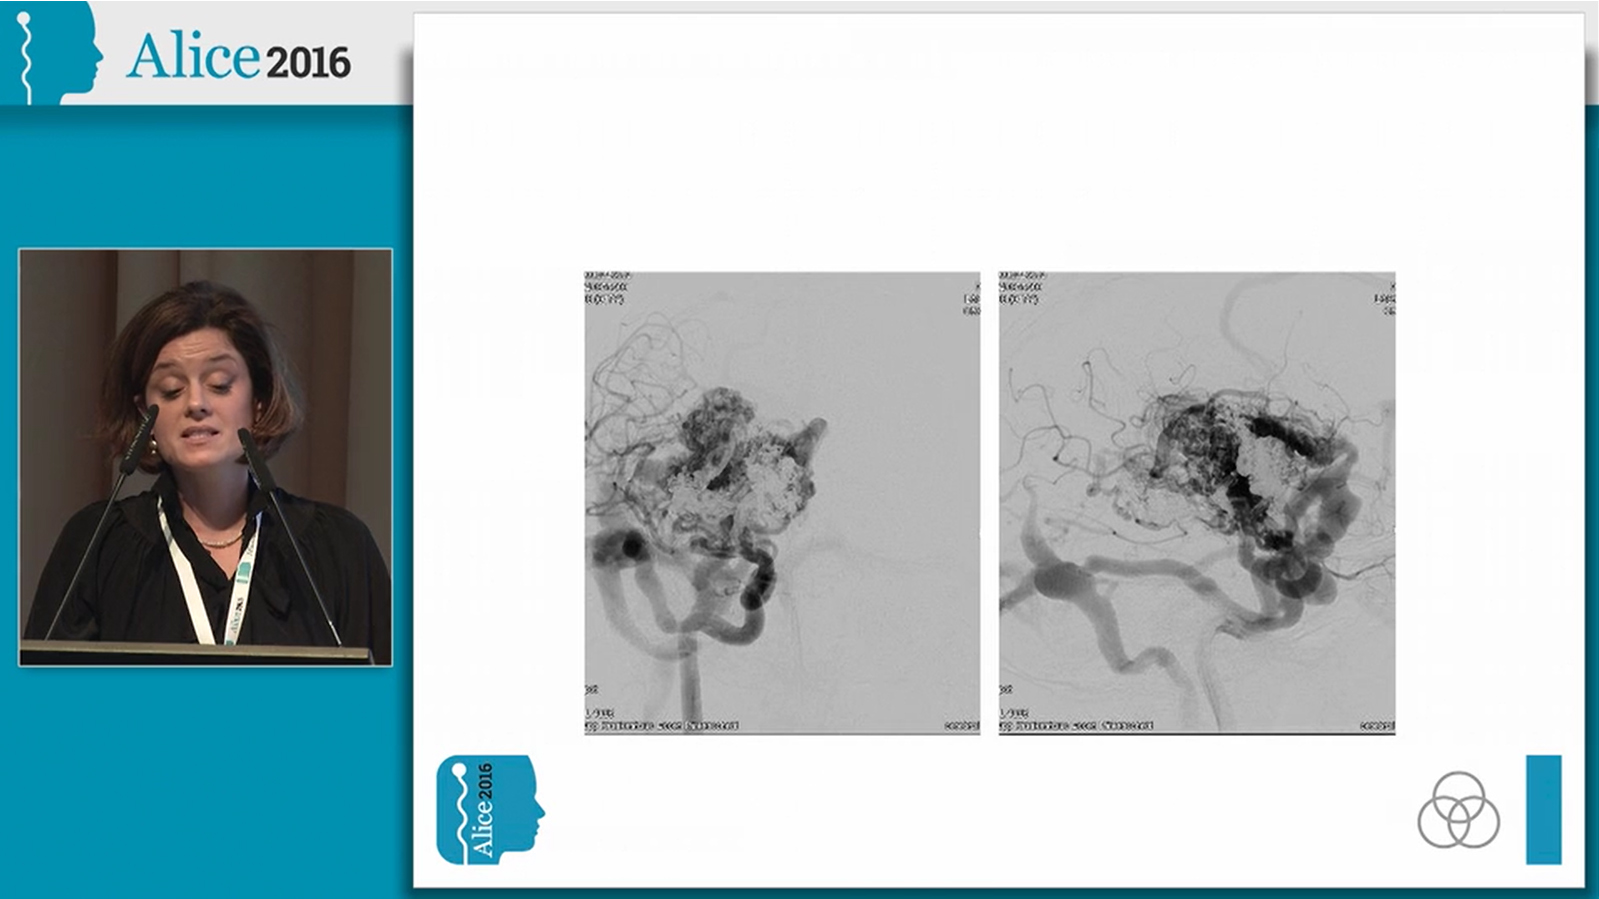

Temporal AVM treated by combined transarterial and transvenous embolization

Watch the video